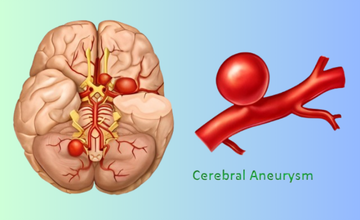

A bulging, weakened blood vessel in the brain that may rupture, causing life-threatening bleeding, headaches, neurological deficits, or stroke.

Minimally invasive technique using soft coils to block aneurysm flow, preventing rupture and ensuring long-term vascular stability.

Provides support for wide-neck aneurysms, ensuring secure coil placement and safer, more effective treatment.

Enhances treatment by redirecting blood flow away from the aneurysm, promoting gradual healing, improving vessel stability, and ensuring stronger, durable protection against future rupture.

Placed directly inside the aneurysm sac, these devices offer targeted treatment with minimal vessel manipulation for improved safety.